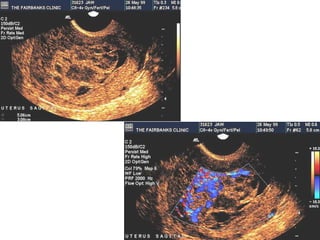

The increasing use of

ultrasound in early

pregnancy has probably

led to the earlier

diagnosis of molar

pregnancy

By the U/S examination can

be diagnosed from very early

pregnancy ,characterized by

“Snow-storm" appearance.